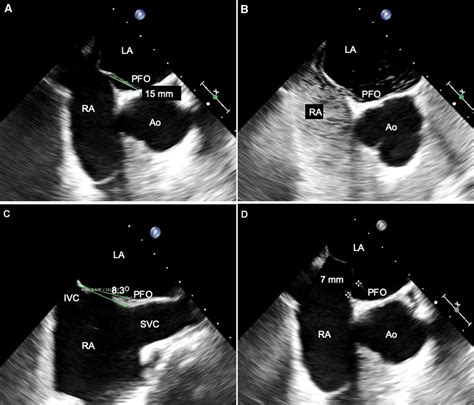

1225×1225

mdpi.com

Advances in Percutaneous Patent Foramen Ovale Closure: From the ...